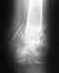

Здравстуйте! Получил полный вывих АКС, при падении на плечо.

Диагноз был поставлен сразу же, при обращении, поставлен я думаю верно, отправили на операцию, предложили фиксацию спицами и лавсаном за клювовидный отросток либо крючковидной пластиной, объяснив что этот метод лучше по трудоемкости операции и жесткости фиксации. Я выбрал пластину, но мне пришлось ждать ее две недели, за это время у меня почти полностью востановилось функциональность руки, она уже почти не болела и двигалась в полном диапазоне, эфект клавиши почти отсутствовал, потому что ключица как-то приросла в вывихнутом состоянии. Однако косметический эффект не оставил мне никаких сомнений и меня прооперировали, поставили пластину, да так что она находится не строго на ключице паралельно полу, а сдвинута немного вперед, из-за этого получилось что прооперированная ключиться у меня находится гораздо ниже здоровой, опять же косметический дефект. Но слава богу прошел месяц после операции, рука потихоньку приходит в норму, однако все еще чувствует себя хуже и не дает двигаться в полном диапазоне движения, так как это было до операции, однако я думаю что это вопрос времени и с каждым днем мне становится все лучше и лучше. Но меня опять же напугал врач у которого я сейчас наблюдаюсь, пластину через год должны убрать, он сказал что когда ее уберут, ключится обратно выскочит в то состояние как до операции и надо оставлять пластину, но эту пластину оставлять нельзя, на ту, которую можно было бы оставить у меня не хватило денег. У меня такой вопрос, действительно ли когда уберут пластину, ключица встанет в состояние вывиха, если да, то зачем тогда нужна такая операция, после которой я после шва на плече кожу вообще не чувствую, нервы отсекли, кстати, тоже вопрос, востановиться ли чувствительность, если же ключица после удаления пластины останется в том положении как она сейчас, можно ли мне будет нагружать руку (я всетаки КМС по пауэрлифтингу и надеюсь продолжить) или при значительной нагрузке будет рецидив? Если нужны снимки, потом выложу, когда с больничного отпустят они в больнице в моей истории болезни.